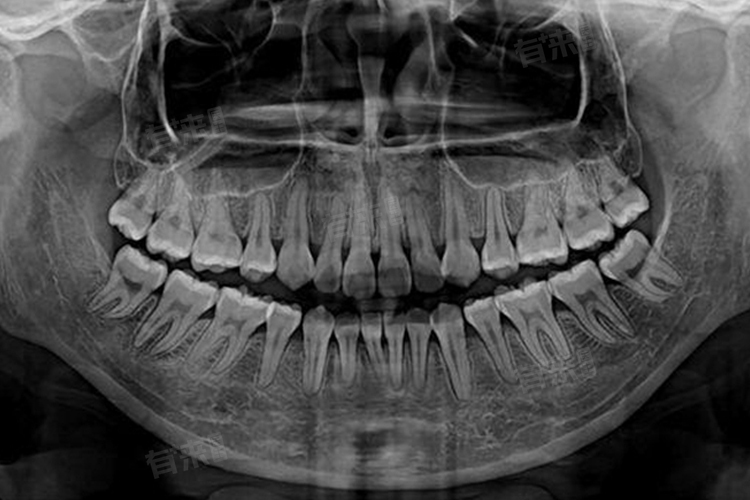

- 而一些更为先进的锥形束CT(CBCT),由于其具有更高的分辨率,能够提供三维立体影像,不仅可以精准呈现牙齿内部细微结构,还能清晰反映出牙齿与周围组织如颌骨、神经、血管的空间关系,对正畸治疗、种植牙手术等复杂口腔诊疗方案的制定提供有力依据,所以价格会偏高,一般在300-500元。

- 检查的复杂程度也是影响价格的关键因素,如果只是简单的单颗牙齿问题排查,如判断一颗智齿的生长方向,操作相对便捷,扫描范围小,耗费的设备资源与时间少,收费可能接近100元。但要是进行全口牙齿的综合检查,像是为正畸全面评估牙列、咬合以及颌骨发育情况,或是排查口腔内多处不明原因的疼痛根源,需要扫描的区域广,图像采集和后期处理的数据量庞大,价格往往会达到较高标准,接近500元。